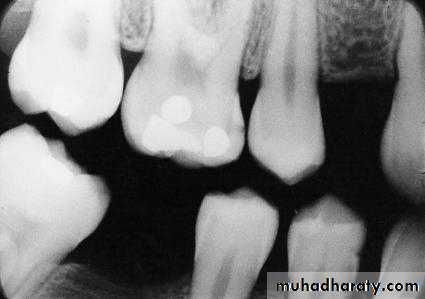

A section of an approximal space between two neighbouring molars with two caries lesions extending into dentine, but without cavity formation. Note the dentine reactions involve all the dentinal tubules affected by the acid attack at the enamel surface.A bitewing radiograph showing caries in enamel and dentine on the mesial aspect of the upper first molar. A lesion is also visible on the mesial aspect of the lower first premolar.